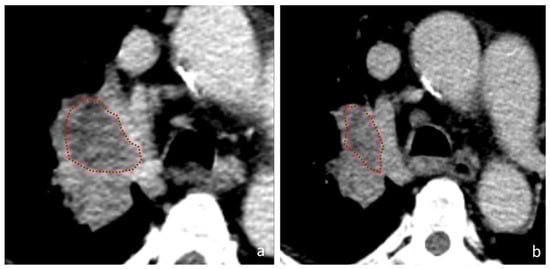

2.3. Segmentation and Radiomic Analysis